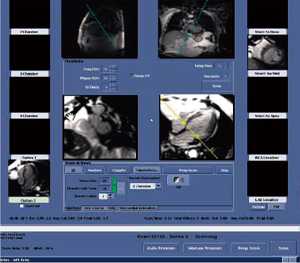

1.Cardiac Viewer

“Cardiac Viewer”は,心臓MRI専用のビューアであり,シネやパーフュージョン,LGEの画像がビューア起動時に自動的に認識される。Review Stepsと呼ばれる複数のプリセットパターンの画像表示がワンクリックで切り替え可能であり,例えばマルチスライス,複数断面のシネ画像を同時に表示したり,シネ画像とLGE画像の比較や,パーフュージョン画像とLGE画像の比較が可能な画面へと,Review Stepsのボタンを押すことで簡単に切り替えることができる(図5)。

図5 Review Stepsによる簡便な画像切り替え